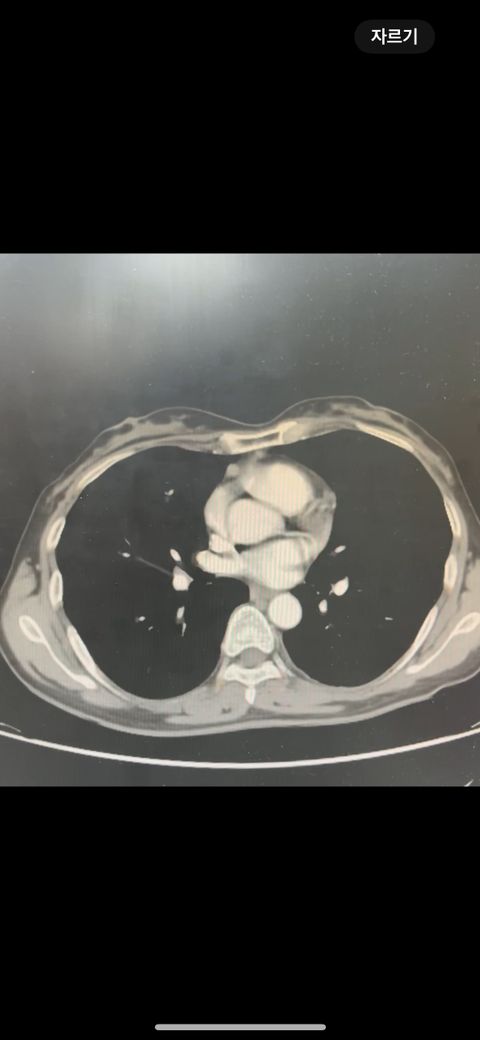

복부 ct (contrast) 영상 판독해주세요!!

어제 복부 ct 촬영하였는데 판독 하려면 시간이 걸려서 미리 알 수 있을까요? 지금 증상은 윗배가 많이 나왔고 허리 아프고 조금만 밥 먹어도 배부른 상태입니다..

• 2번 째 사진

어제 말씀드린대로 자궁 쪽에 불규칙한 음영들이 보이고 있어 물혹이 있는 것으로 의심해 볼 수 있으며, 이외에 복부에 가스가 조금 차있거나 비장이 약간 커져 있는 듯한 모습이 보이나 일부 단면만으로 유추한 것이라 판독 상 틀릴 가능성도 있겠습니다.